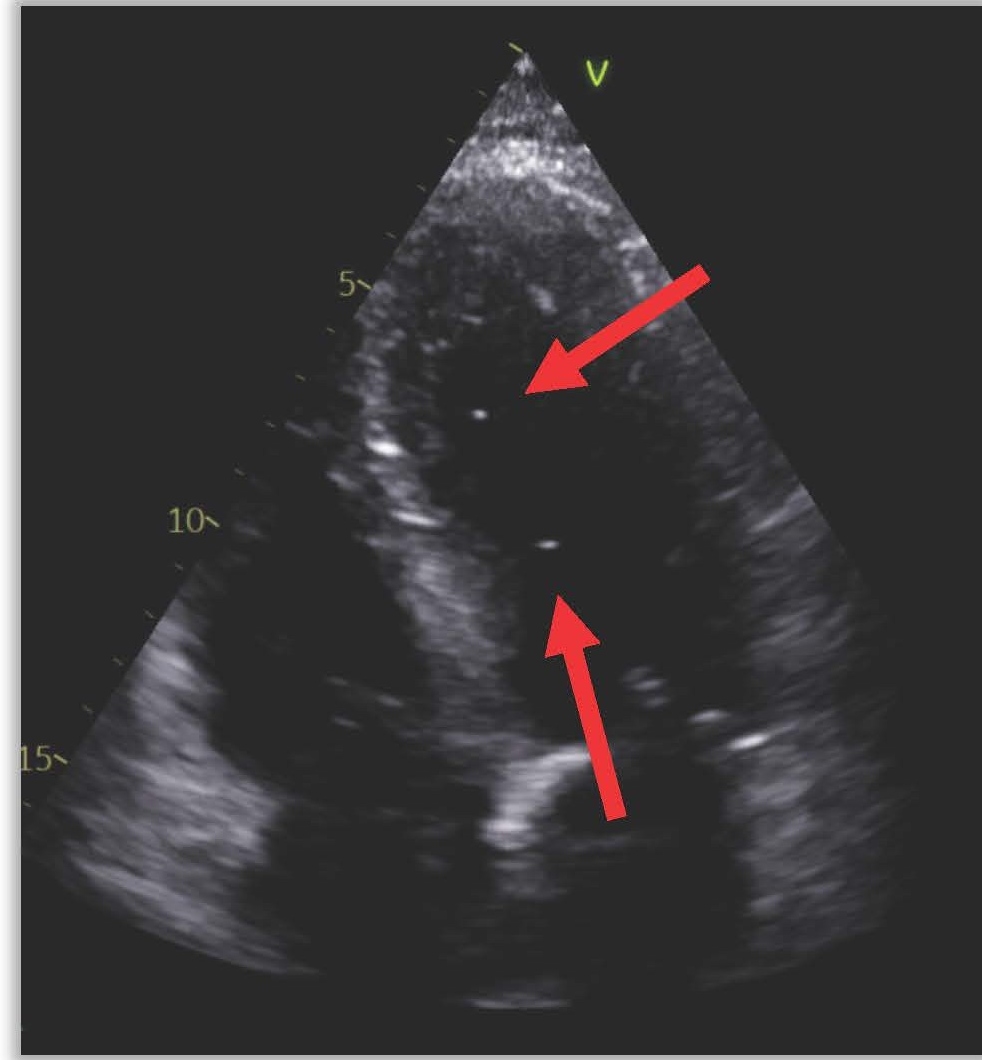

The next day (25 days post-ablation), the patient experienced significant neurological deterioration, with a GCS score dropping to 3/15, supraventricular tachycardia at 122 beats per minute, severe hypotension, and tachypnea with a respiratory rate of 36 per minute. A purpuric rash appeared on the neck, chest, and shoulders, and the patient was febrile with a temperature of 40°C. Due to the severe neurological and septic presentation, he was admitted to the ICU, intubated, and placed on mechanical ventilation. Invasive monitoring and hemodynamic support were initiated. Blood tests showed a marked increase in C-reactive protein (210 mg/L), a white blood cell count of 7.16 x 10^3/µL (65% neutrophils), and significant renal function deterioration. First blood cultures identified multisensitive Streptococcus salivarius, leading to the initiation of antibiotic therapy with amikacin and ceftriaxone for suspected endocarditis. The lumbar puncture was sterile. Transesophageal echocardiography (TEE) later revealed a highly echogenic mass attached to the left pulmonary vein's ostium (Figure 1), severe left ventricular dysfunction, and air bubbles in cardiac cavities (Figure 2). A contrast-enhanced thoracic CT scan showed air in the left atrium and findings consistent with mediastinitis (Figure 3).

Figure 2. TEE showing air bubbles in intracardiac cavities.

Figure 3. Air present in the left atrium and communication between esophagus and LA.